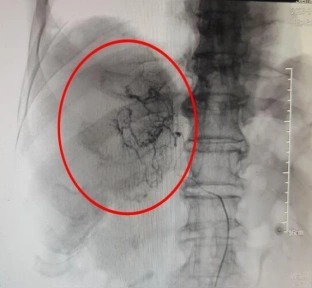

鉴于患者病情危急,传统开腹手术创伤大、风险高,肿瘤微创介入诊疗中心手术团队紧急会诊后,决定为其施行经肝动脉化疗栓塞术(TACE)。术中医生通过股动脉穿刺插入导管鞘,在导丝引导下将导管送至腹主动脉,注入造影剂进行血管造影,清晰显示肿瘤的位置、大小及供血动脉分支。再将微导管选择性插入肿瘤供血动脉,先灌注化疗药物,再注入栓塞剂,精准阻断出血血管,同时切断肿瘤营养供应。术后患者生命体征平稳,腹痛症状明显缓解。复查CT显示,肿瘤出血已完全停止,肿瘤染色消失。

栓塞术后肿瘤染色消失